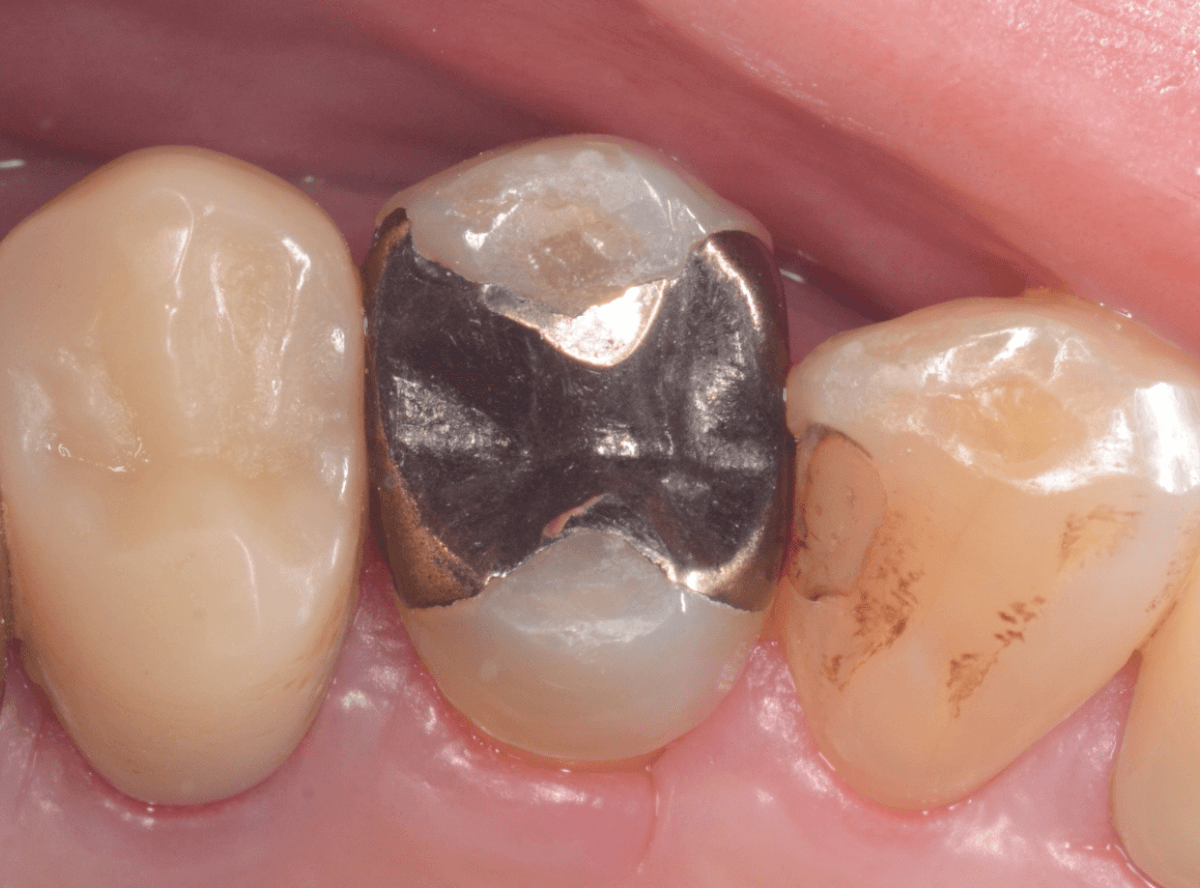

メタル・インレーとメタル・クラウンが入っていますね。

まずは、奥のメタル・クラウンを外します。

メタル・コアが入っていますが、こちらも慎重に外して、中を調べていきます。

レントゲン写真では問題なさそうでしたが、メタルコアを除去すると、中は真っ黒でした。

このように、コアの中で虫歯が進行している場合もありますので、さし歯をやり直す際は、出来る限りコアも外して調べるようにしています。